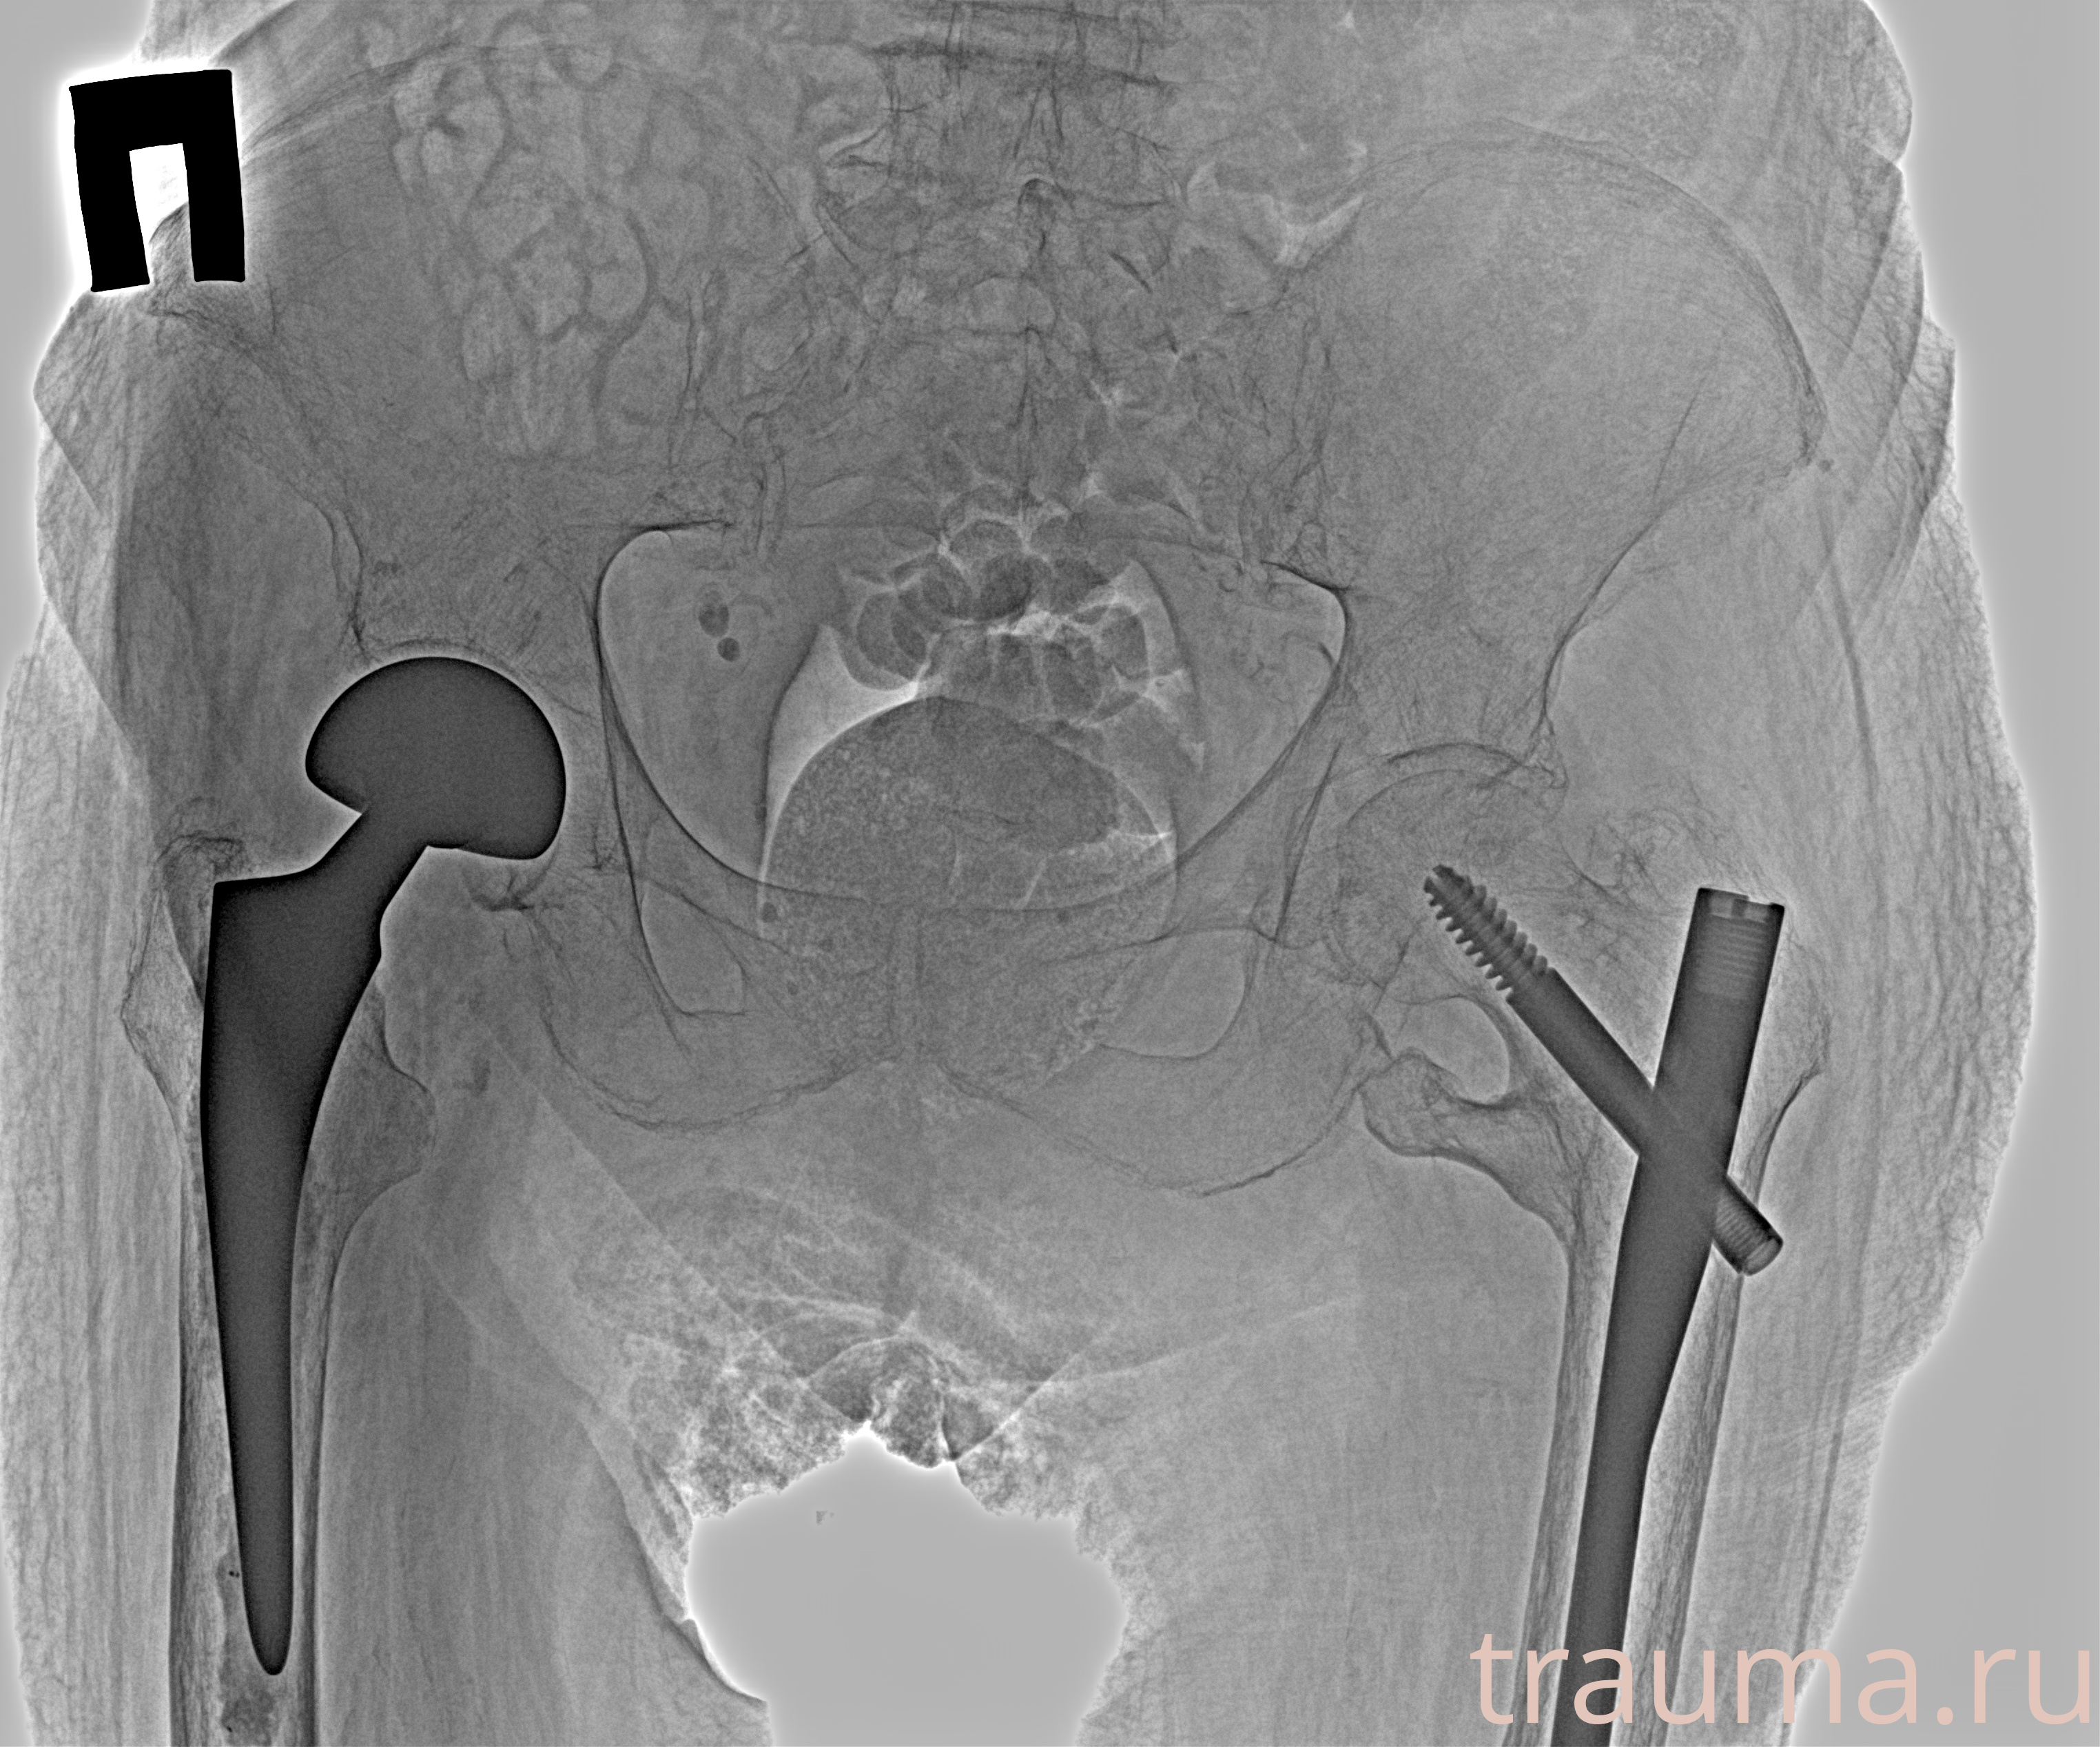

Рентген на дому: по вашему адресу приезжает врач-рентгенолог, травматолог-ортопед с мобильным рентгеновским аппаратом, проводит диагностику травмы или заболевания, делает необходимые рентгенограммы, дает рекомендации по дальнейшему лечению. Получить качественные снимки в домашних условиях возможно благодаря уникальной методике, разработанной МосРентген Центром для института  Склифосовского